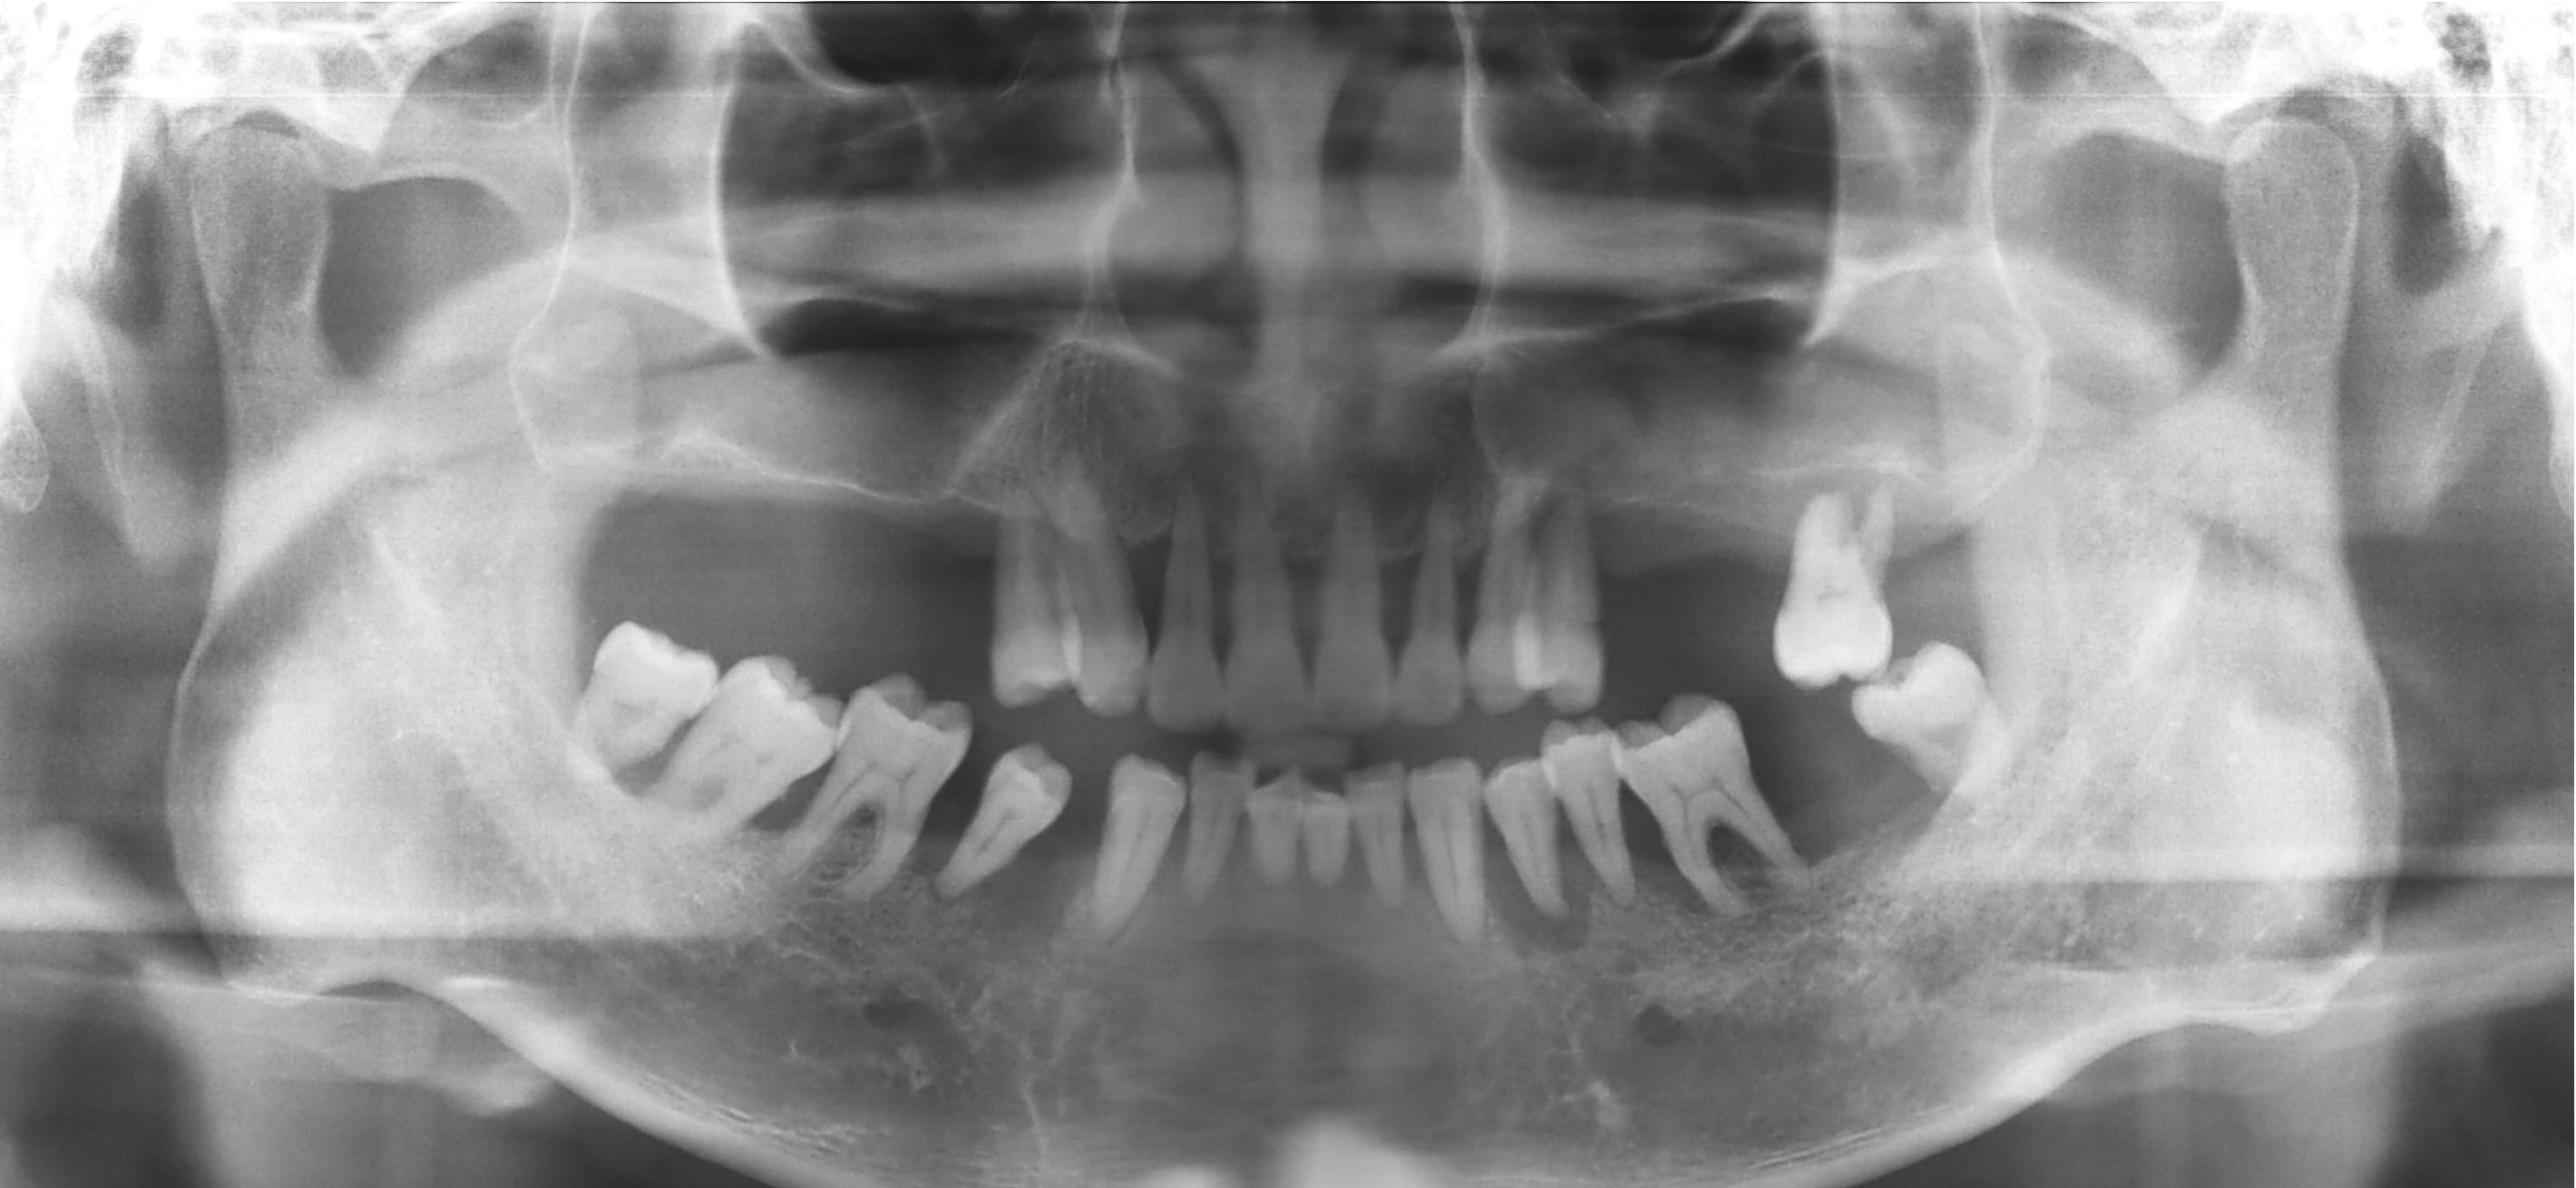

Before

상악동거상술 Sinus